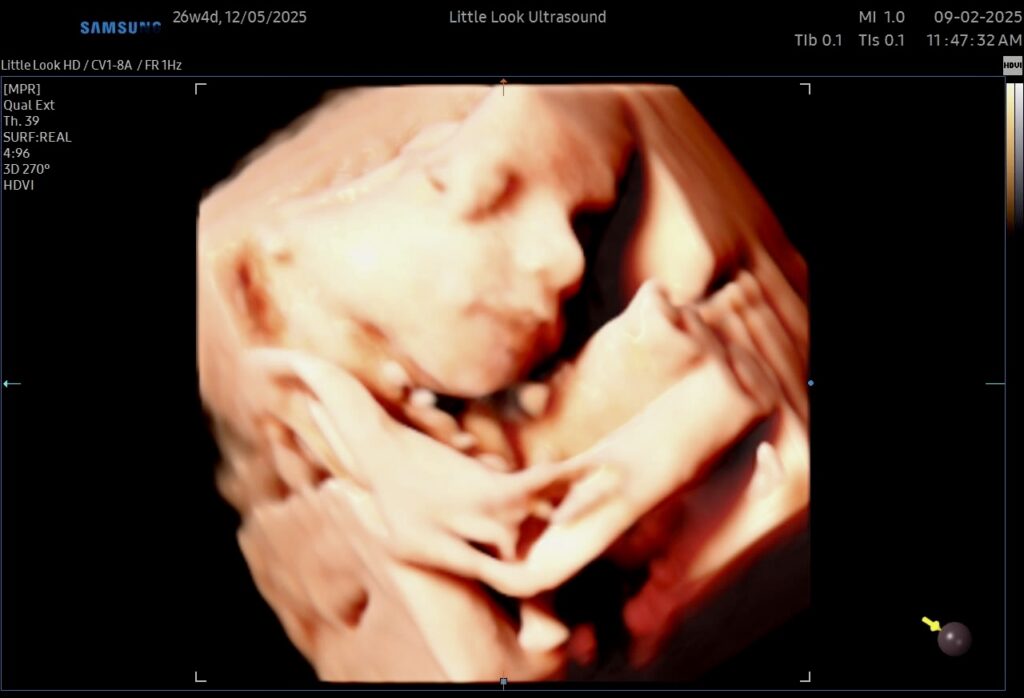

- 3D Ultrasound Pictures – Realistic, detailed images that show your baby’s unique features.

- Early Connection – See your baby’s face, expressions, and movements before birth.

- 3D 4D State of the Art Technology – High-resolution imaging with keepsake options to cherish.